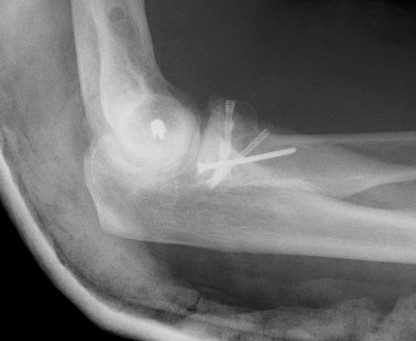

Technique Modular Titanium Radial Head Arthroplasty

Lateral approach to elbow / Kaplans or Kocher

- open capsule

- divide annular ligaments

- excise radial head fragments

- use fragments to estimate diameter and thickness of radial head

- if in doubt, downsize

- deliver radial neck

- do not place Hohman retractor anteriorly to protect PIN

- ensure neck cut flat to avoid maltracking

- want 60% contact of radial neck with prosthesis

- insert trial broaches into neck

- insert trial head diameter and neck length

- check no overstuffing on xray

- insert prosthesis

- repair annular ligament

- inspect +/- repair LCL